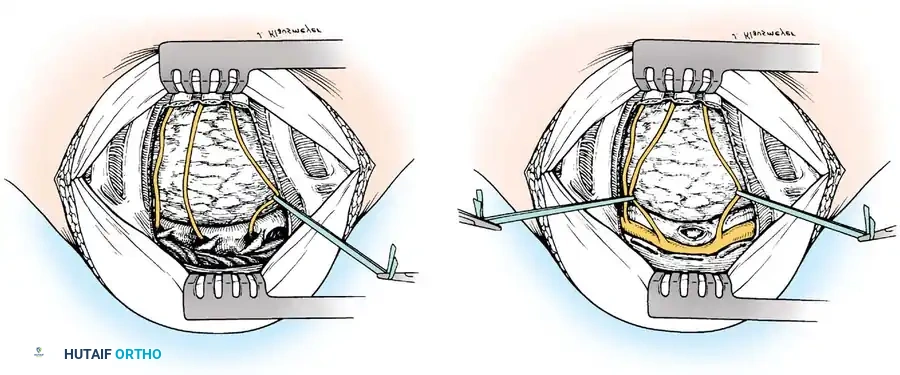

- Palpate the extent of the abscess across the anterior vertebral bodies. Make a T-shaped incision through the thick abscess wall: the transverse limb should be opposite the center of the disease, and the longitudinal limb medial to the ligated intercostal vessels.

- Raise the two triangular flaps to reveal the caseous necrotic core and the destroyed vertebral bodies.

Radical Débridement (Corpectomy)

- Evacuate all liquid pus, caseous debris, and sequestrated bone or disc material using high-powered suction and pituitary rongeurs. If the abscess spans bilaterally, pass the suction tip anterior to the vertebrae into the contralateral cavity to ensure complete evacuation.

- Using osteotomes, high-speed burrs, and rongeurs, radically excise all diseased, sclerotic, and necrotic bone.

- The excision must extend posteriorly to the posterior longitudinal ligament (PLL). Remove the PLL and any tuberculous granulation tissue to fully decompress the ventral dura.

- Crucial Step: Excise the entire affected vertebral body. Tuberculous collections and sequestrated disc fragments frequently hide in the spinal canal posterior to seemingly intact posterior vertebral body walls.

- Remove the intervertebral discs at the cranial and caudal extents of the cavity until normal, bleeding endplates are exposed.

Structural Arthrodesis

- Attempt partial correction of the kyphotic deformity by applying direct posterior pressure on the spine (often done by the anesthesia team or via positioning).

- Cut a deep, precise mortise (keyhole) into the healthy vertebral bodies at both the superior and inferior ends of the defect.

- Measure the defect and insert one or more structural strut grafts. The grafts must be slightly oversized to keep the vertebrae "sprung apart" under compression, ensuring immediate biomechanical stability and preventing graft dislodgment.